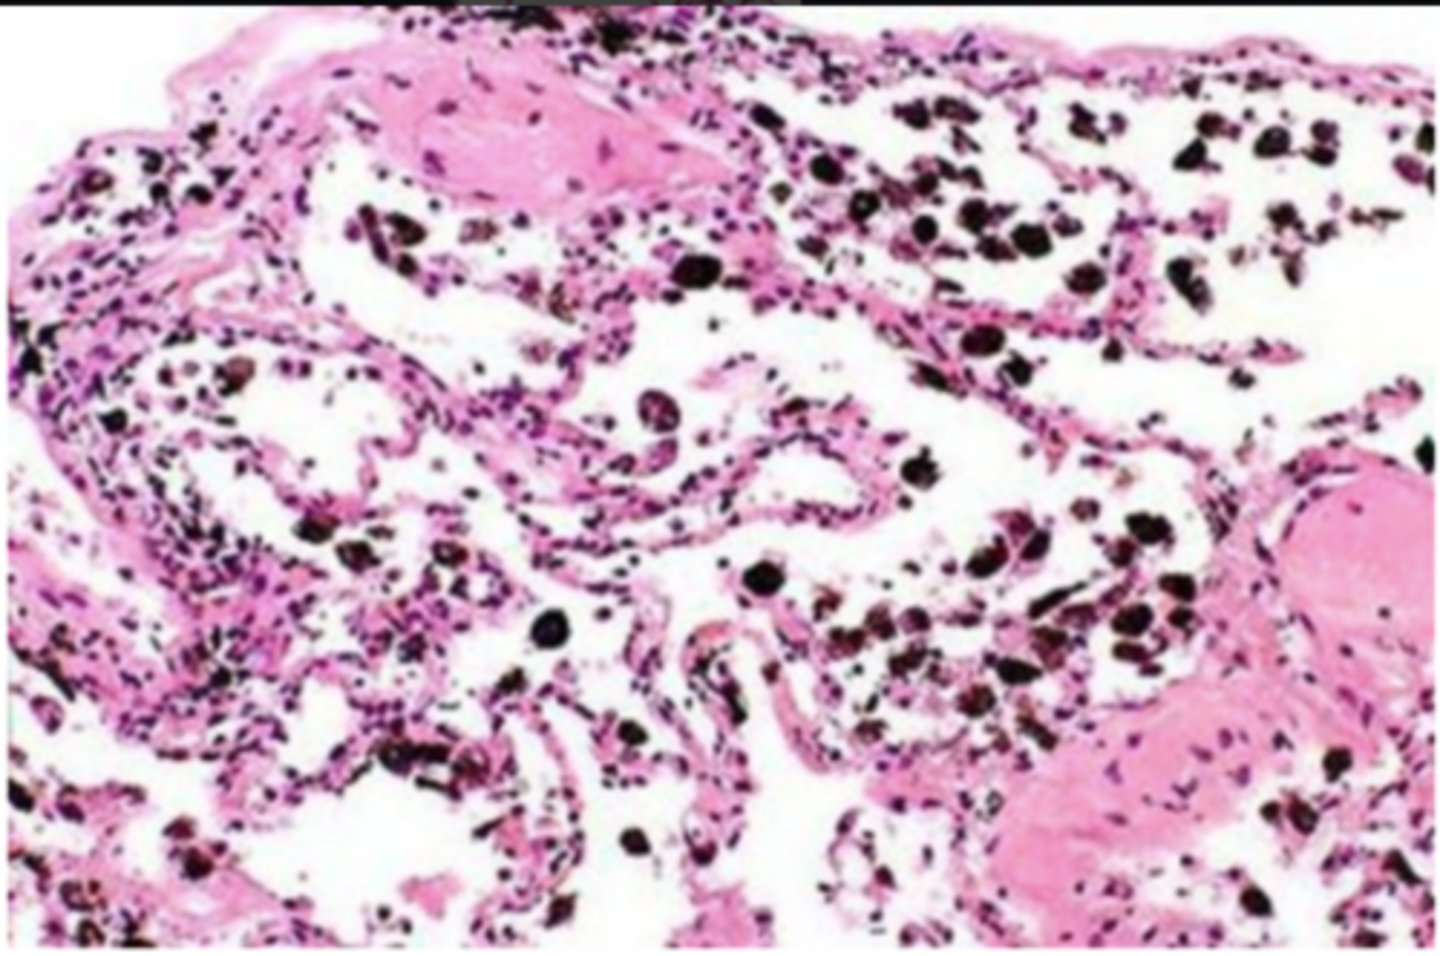

smoker's lung

alveolus (of smoker's lung)

carbon deposits (tar)